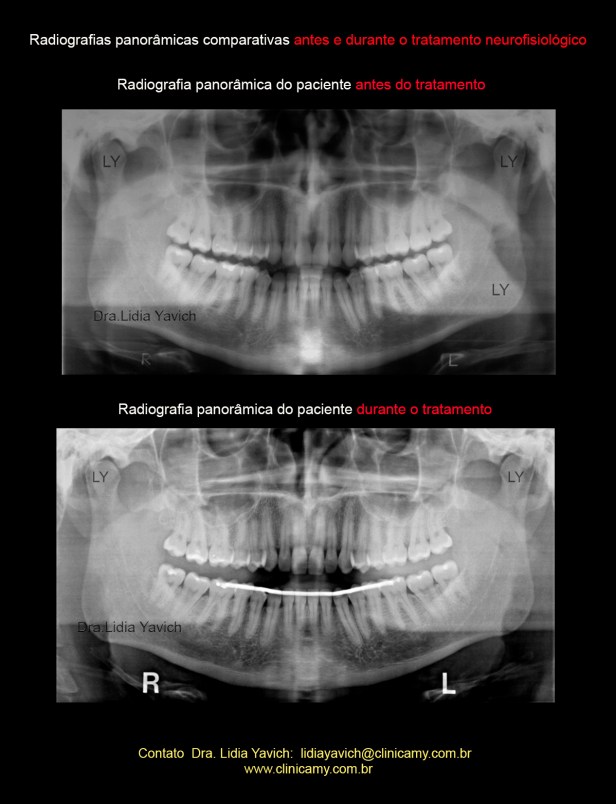

Radiografia panorâmica do paciente antes do tratamento.

Radiografias panorâmicas comparativas: antes do tratamento e durante o tratamento neuromuscular fisiológico.